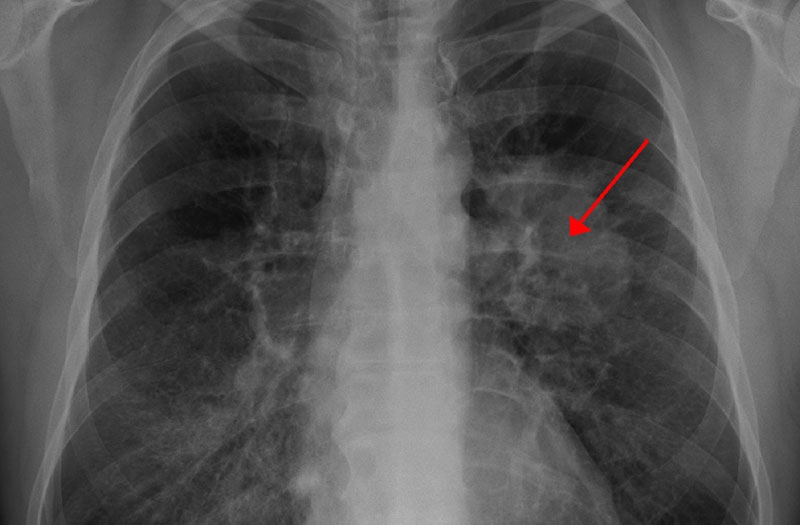

Các khối u phổi trên phim X-quang có hình thái đa dạng nhưng thường biểu hiện dưới dạng khối mờ (vùng sáng trên phim), có hình tròn với ranh giới có thể rõ hoặc không. Dựa vào vị trí xuất hiện, u phổi được chia thành hai loại chính:

– U phổi trung tâm: Xuất hiện ở vùng rốn phổi, thường có hình ảnh khối mờ tại rốn phổi, với bờ tua gai (dạng tia nắng mặt trời) và ranh giới không rõ ràng. Do xuất phát từ các phế quản lớn, loại u này có thể gây xẹp thùy phổi nếu xâm lấn vào nhánh phế quản.

– U phổi ngoại vi: Xuất hiện ở vùng ngoại vi phổi, thường có hình tròn hoặc bầu dục, với bờ rõ nét hơn so với u trung tâm.

Ngoài hình ảnh của ung thư nguyên phát tại phổi, X-quang còn có thể phát hiện các tổn thương di căn từ ung thư ở cơ quan khác. Khi đó, phim X-quang có thể xuất hiện các nốt mờ nhỏ, kích thước không đồng đều, rải rác hai bên phổi, thường được gọi là hình ảnh “thả bóng”.

Chụp X-quang phổi là một phương pháp quan trọng giúp bác sĩ đánh giá sơ bộ các tổn thương tại phổi, đặc biệt có giá trị trong tầm soát ung thư phổi. Nếu phim X-quang phát hiện các dấu hiệu nghi ngờ tổn thương ác tính như khối mờ vùng rốn phổi, bờ tua gai, ranh giới không rõ hoặc hình ảnh “thả bóng” hai trường phổi, bác sĩ sẽ xem xét thêm các triệu chứng lâm sàng và chỉ định các phương pháp chẩn đoán chuyên sâu như chụp cắt lớp vi tính, xét nghiệm máu hoặc sinh thiết u phổi,… để đưa ra kết luận chính xác.